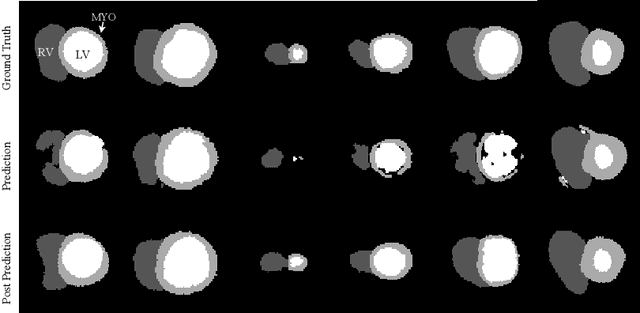

Abstract:Performance of deep learning segmentation models is significantly challenged in its transferability across different medical imaging domains, particularly when aiming to adapt these models to a target domain with insufficient annotated data for effective fine-tuning. While existing domain adaptation (DA) methods propose strategies to alleviate this problem, these methods do not explicitly incorporate human-verified segmentation priors, compromising the potential of a model to produce anatomically plausible segmentations. We introduce RL4Seg, an innovative reinforcement learning framework that reduces the need to otherwise incorporate large expertly annotated datasets in the target domain, and eliminates the need for lengthy manual human review. Using a target dataset of 10,000 unannotated 2D echocardiographic images, RL4Seg not only outperforms existing state-of-the-art DA methods in accuracy but also achieves 99% anatomical validity on a subset of 220 expert-validated subjects from the target domain. Furthermore, our framework's reward network offers uncertainty estimates comparable with dedicated state-of-the-art uncertainty methods, demonstrating the utility and effectiveness of RL4Seg in overcoming domain adaptation challenges in medical image segmentation.

Abstract:Convolutional neural networks (CNN) have had unprecedented success in medical imaging and, in particular, in medical image segmentation. However, despite the fact that segmentation results are closer than ever to the inter-expert variability, CNNs are not immune to producing anatomically inaccurate segmentations, even when built upon a shape prior. In this paper, we present a framework for producing cardiac image segmentation maps that are guaranteed to respect pre-defined anatomical criteria, while remaining within the inter-expert variability. The idea behind our method is to use a well-trained CNN, have it process cardiac images, identify the anatomically implausible results and warp these results toward the closest anatomically valid cardiac shape. This warping procedure is carried out with a constrained variational autoencoder (cVAE) trained to learn a representation of valid cardiac shapes through a smooth, yet constrained, latent space. With this cVAE, we can project any implausible shape into the cardiac latent space and steer it toward the closest correct shape. We tested our framework on short-axis MRI as well as apical two and four-chamber view ultrasound images, two modalities for which cardiac shapes are drastically different. With our method, CNNs can now produce results that are both within the inter-expert variability and always anatomically plausible without having to rely on a shape prior.

Abstract:Recent publications have shown that the segmentation accuracy of modern-day convolutional neural networks (CNN) applied on cardiac MRI can reach the inter-expert variability, a great achievement in this area of research. However, despite these successes, CNNs still produce anatomically inaccurate segmentations as they provide no guarantee on the anatomical plausibility of their outcome, even when using a shape prior. In this paper, we propose a cardiac MRI segmentation method which always produces anatomically plausible results. At the core of the method is an adversarial variational autoencoder (aVAE) whose latent space encodes a smooth manifold on which lies a large spectrum of valid cardiac shapes. This aVAE is used to automatically warp anatomically inaccurate cardiac shapes towards a close but correct shape. Our method can accommodate any cardiac segmentation method and convert its anatomically implausible results to plausible ones without affecting its overall geometric and clinical metrics. With our method, CNNs can now produce results that are both within the inter-expert variability and always anatomically plausible.